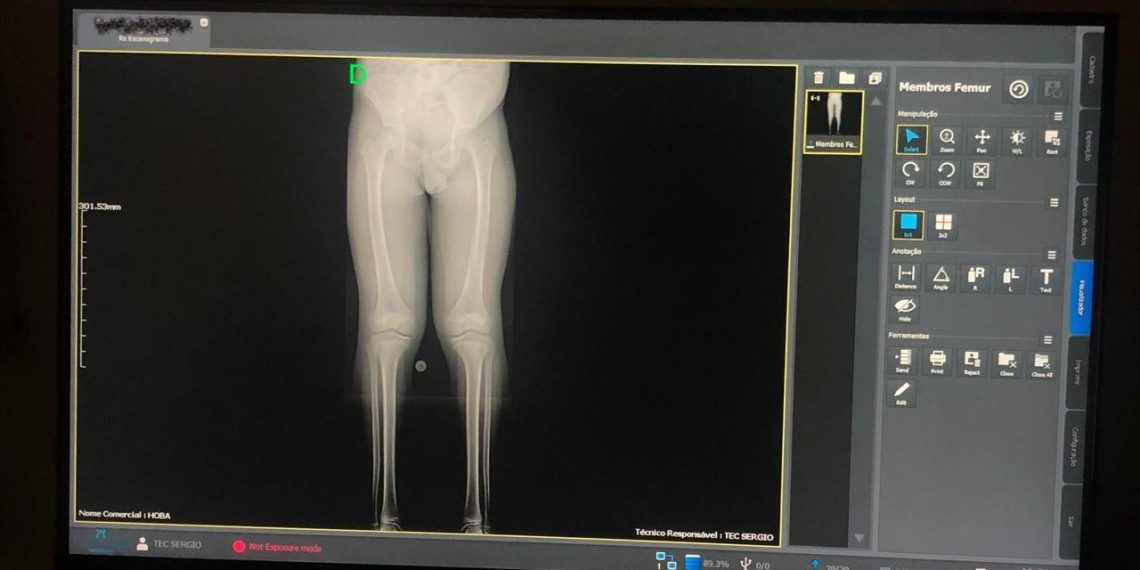

O Hospital Ortopédico do Estado da Bahia, que é gerido pelo Einstein e possui atendimento 100% público, oferece de forma inédita aos pacientes do SUS no estado o exame de escanometria. O procedimento, uma espécie de Rx digitalizado, antes disponível na Bahia apenas na rede privada de saúde, realiza medidas do corpo e dos membros do paciente, permitindo avaliar com precisão o crescimento e o desenvolvimento dos ossos, assim como os desvios da coluna vertebral, que acometem faixas específicas da população.

A escanometria ajuda a identificar diversos problemas com antecedência, entre eles deformidades e lesões traumáticas, além de contribuir na preparação e acompanhamento de tratamentos cirúrgicos e clínicos envolvendo ossos e articulações. “O exame auxilia a equipe médica a entender melhor as necessidades específicas de cada paciente, contribuindo para um diagnóstico mais preciso e um plano de tratamento mais adequado, como o uso de órteses, por exemplo”, explica Niklas Söderberg, gerente médico do Hospital Ortopédico do Estado da Bahia.

O exame é ideal para verificar alterações estruturais nos membros, coluna e até no alinhamento das pernas e dos braços. O procedimento passou a fazer parte do moderno centro de bioimagem do hospital, ampliando sua capacidade de atendimento. Na unidade, já foram realizados 329 escanometria, nos quais foram possíveis observar de forma detalhada toda a estrutura óssea dos pacientes, por meio de sensores extremamente precisos, facilitando e acelerando o diagnóstico médico.